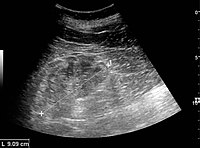

Ultrasound[edit | edit source]

Kidney ultrasonography is useful for diagnostic and prognostic purposes in chronic kidney disease. Whether the underlying pathologic change is glomerular sclerosis, tubular atrophy, interstitial fibrosis or inflammation, the result is often increased echogenicity of the cortex. The echogenicity of the kidney should be related to the echogenicity of either the liver or the spleen (Figure 22 and Figure 23). Moreover, decreased kidney size and cortical thinning are also often seen and especially when disease progresses (Figure 24 and Figure 25). However, kidney size correlates to height, and short persons tend to have small kidneys; thus, kidney size as the only parameter is not reliable.[44]